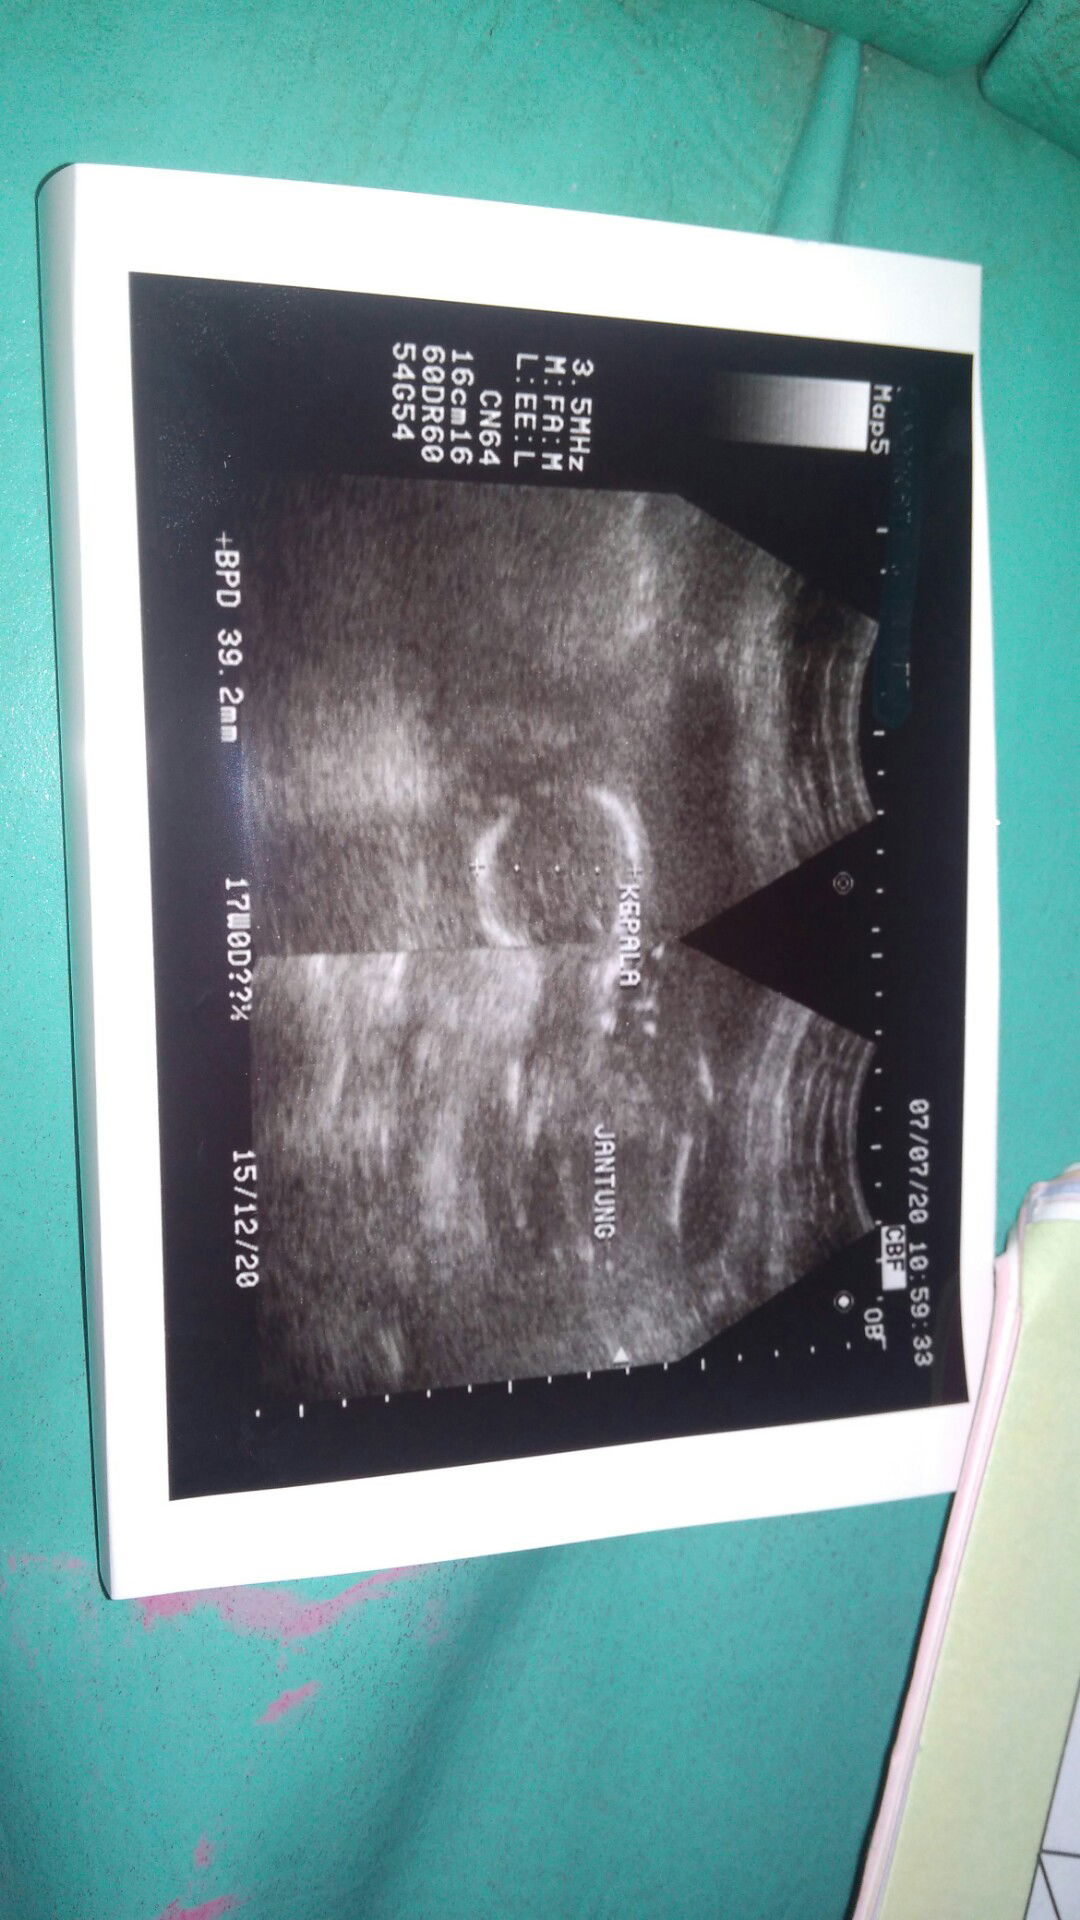

hasil usg

Bagaimana cara membaca hasil usg Bun. Ngga ngerti ..

Nanya dokternya lah bun, ahlinya. Suruh jelasin aja. Hak kita kok, kan bayar. Kalau masih awal2, jantungnya udah bisa diliat detaknya. Yang penting ukuran2 janin sesuai usianya ga. Plasenta ada masalah ga. Air ketuban cukup ga.